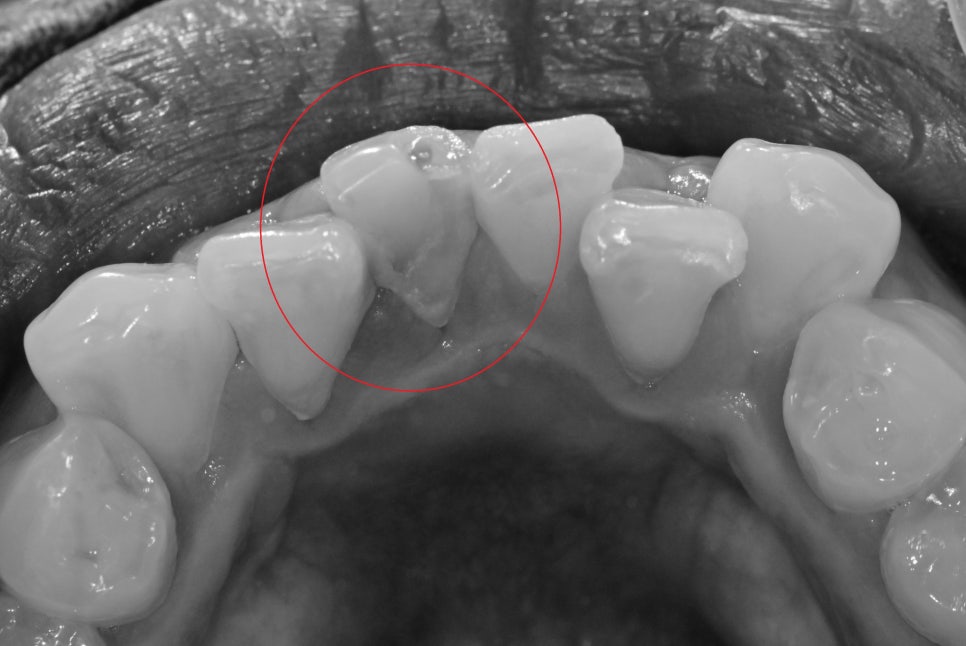

이 환자분 같은 경우는 치아의 크기가 작은 곳이고

치열이 고르지 않고 보철을 위해 치아를 다듬는 과정에서

남아있는 치아의 양이 너무 작아 파절의 위험성이 있기 때문에

레진을 이용한 build-up 치료를 하기로 결정을 했습니다.

크라운 같은 보철이 아닌 진료실에서 직접 레진을 이용해

치아의 외형을 만들고 교합을 체크하기 때문에

진료시간이 좀 길어졌습니다.

레진으로 치료를 완료했기 때문에 대합치와 교합 간섭을 신경 써서

교합조정을 해서 최대한 오래 유지할 수 있게 해드렸습니다.